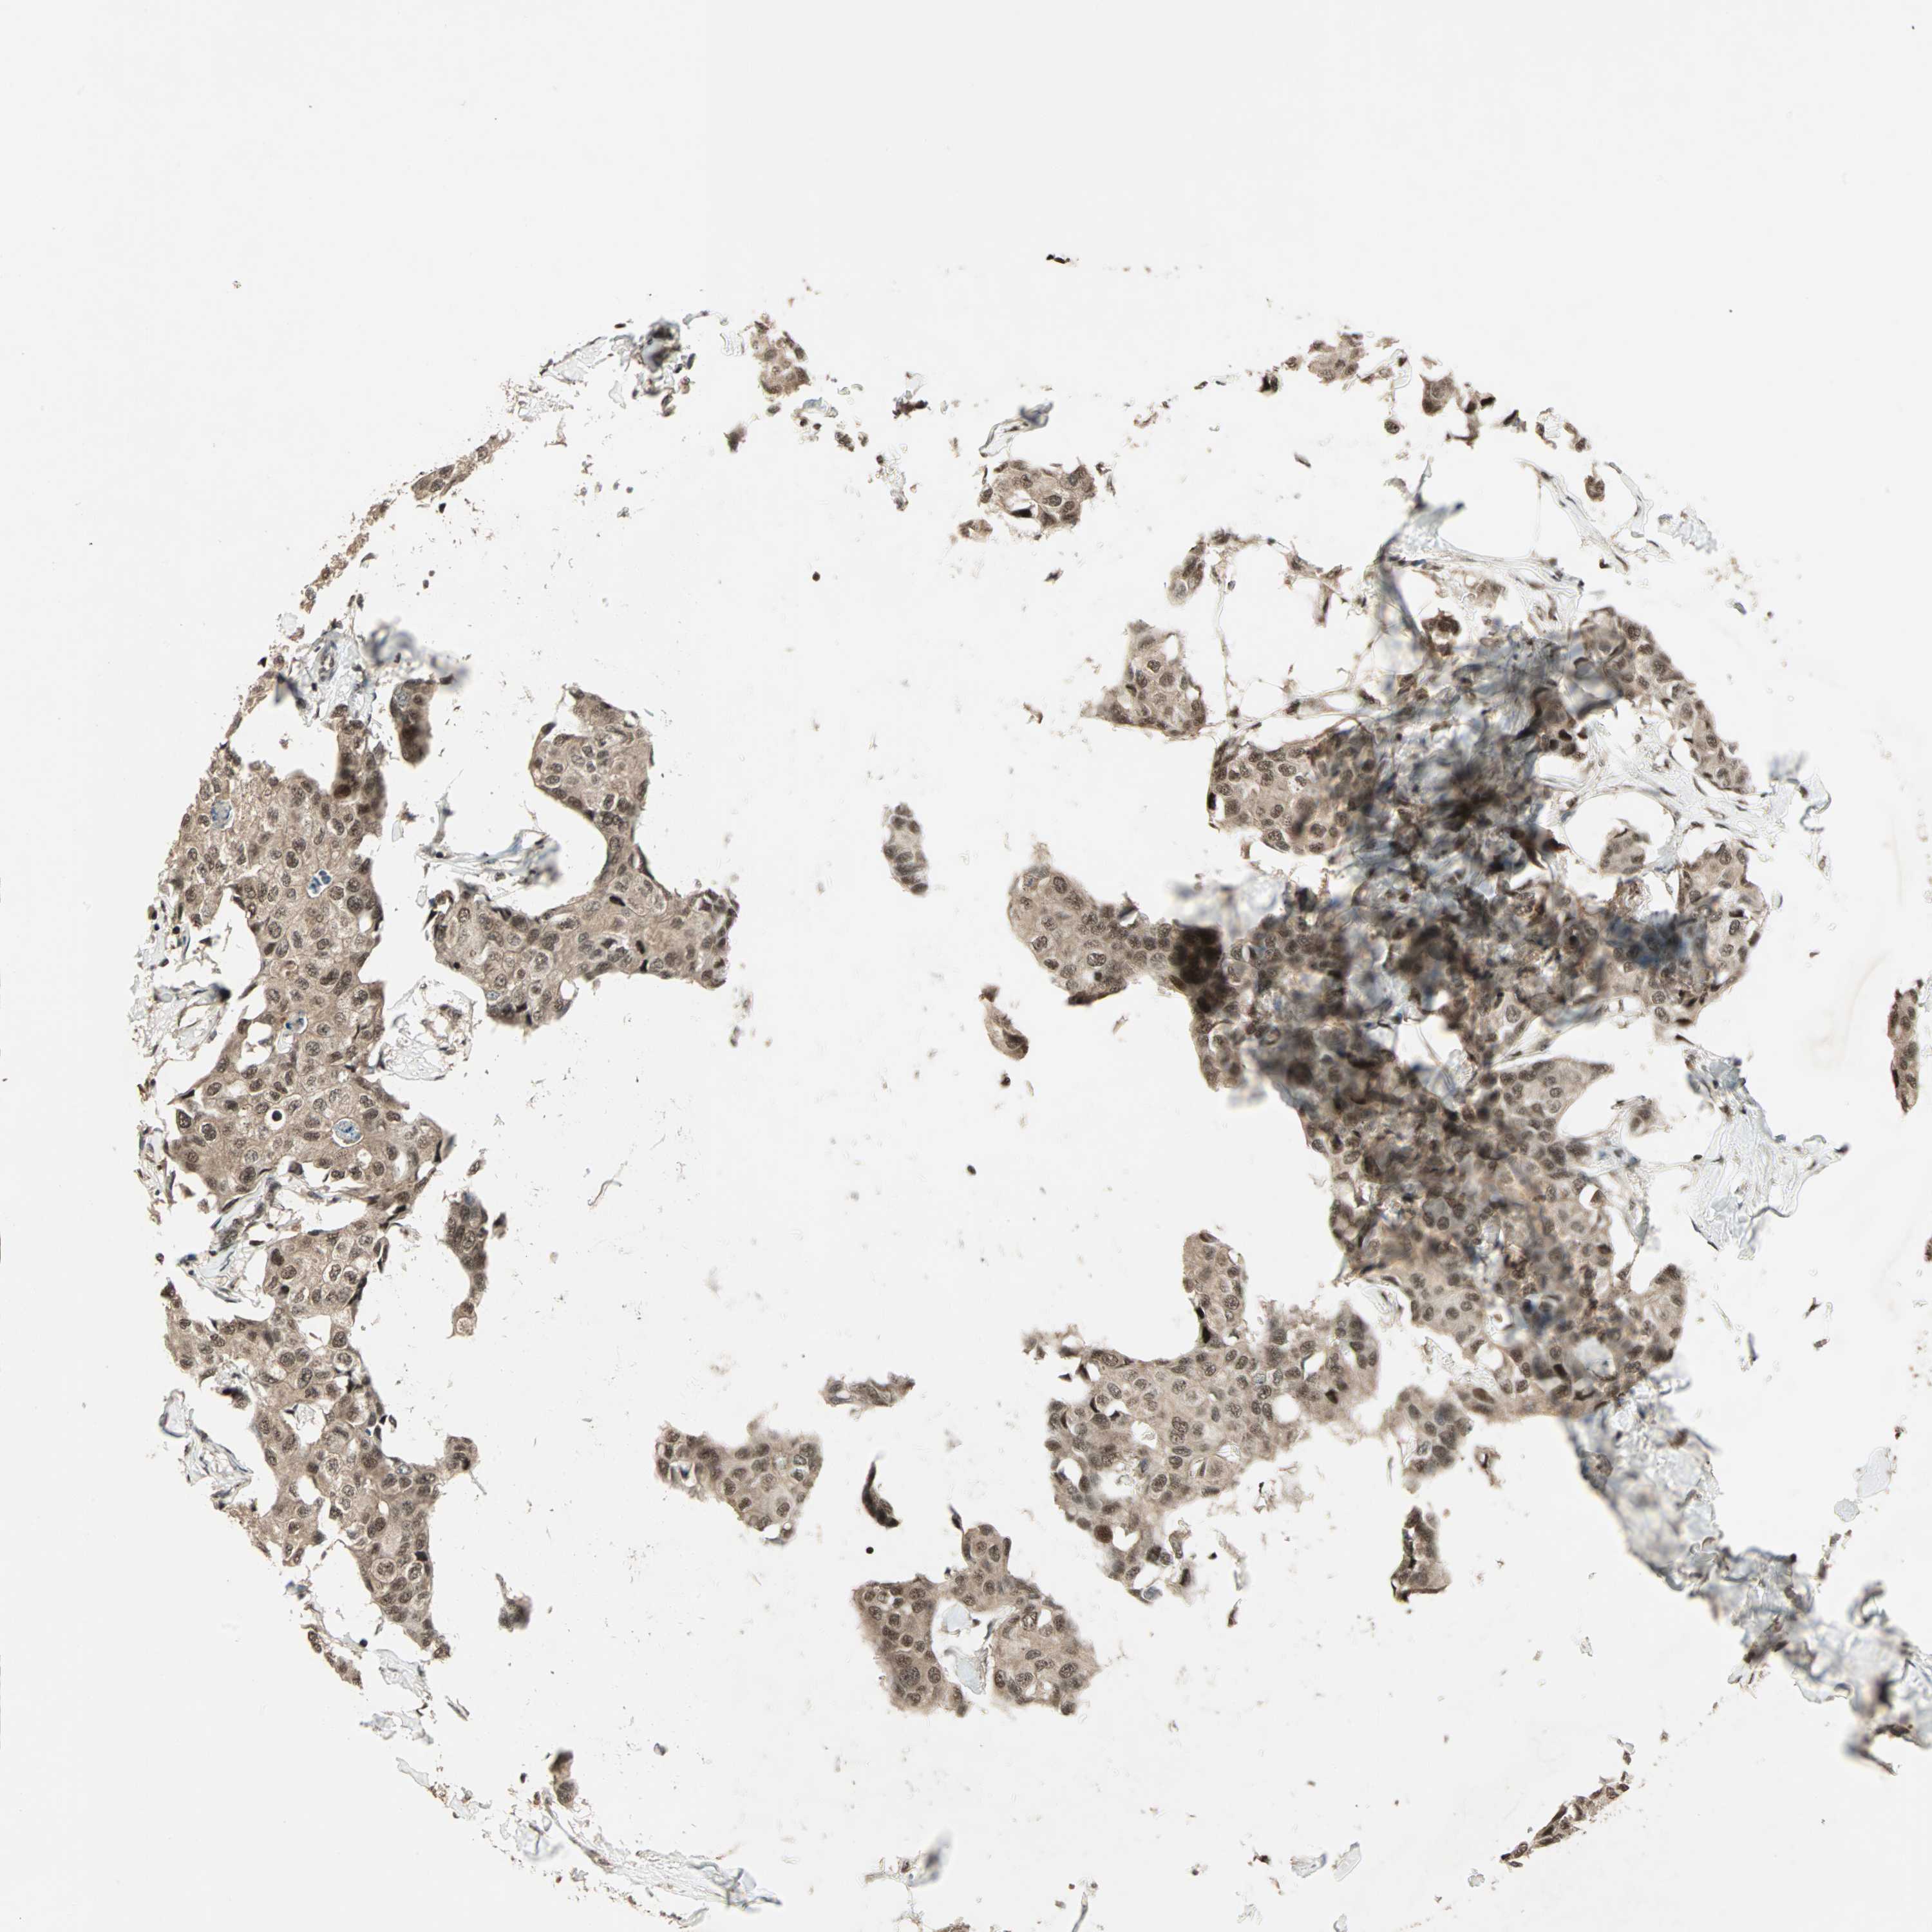

BRCA TCGA BRCA VALIDATION PROTEIN EXPRESSION

Breast cancer

Human cancer